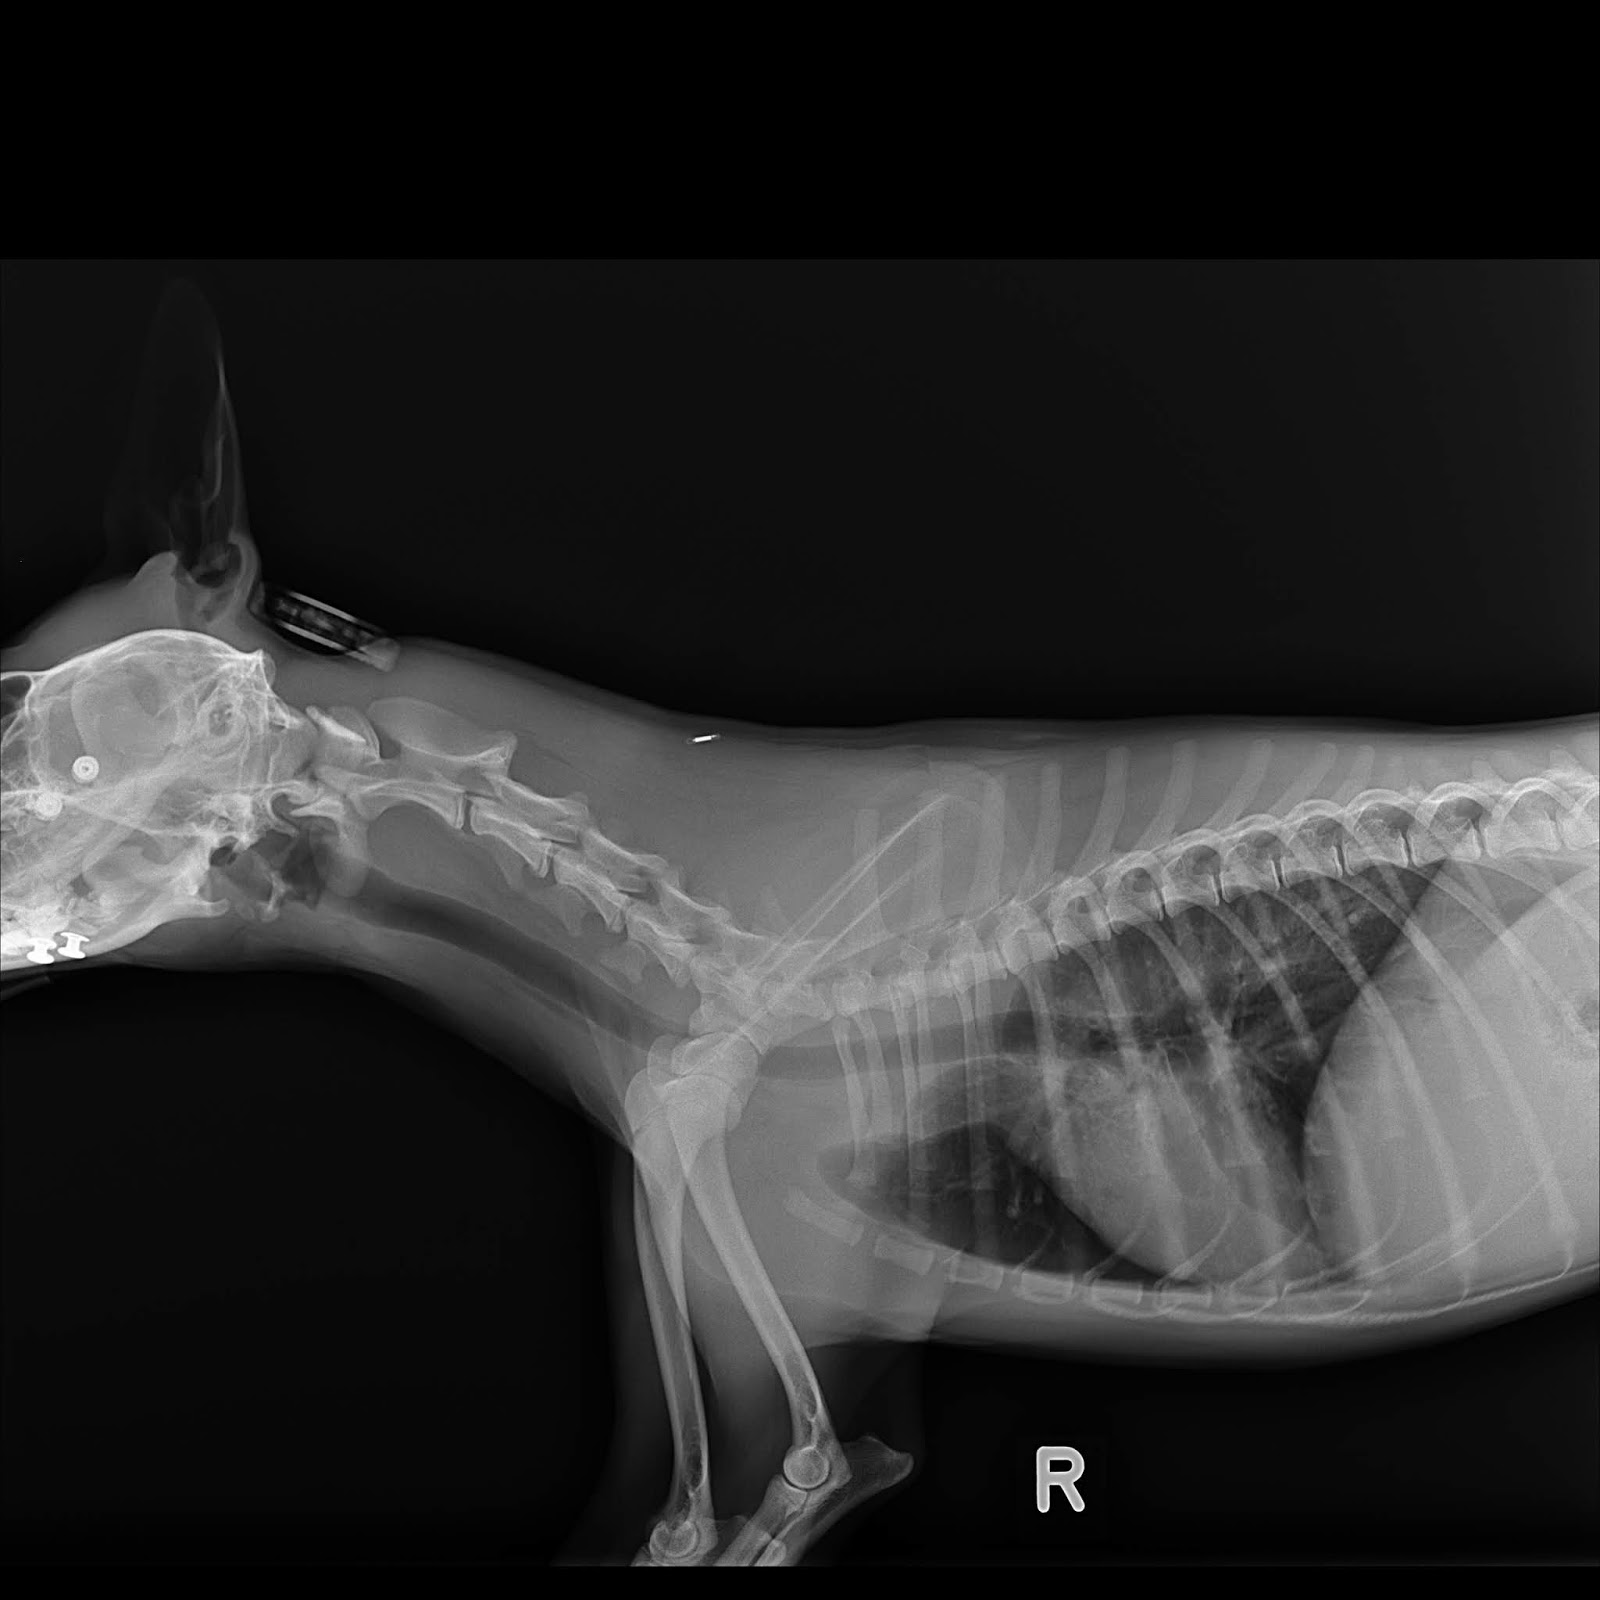

From www.dunelmvetsdurham.co.uk

dogxray Dunelm Veterinary Group Kennel Cough Xray Are you noticing your dog has a runny nose and a sudden, harsh cough that sounds like a goose honking? Thoracic radiographs are recommended for any patient with: There’s a good chance they’re suffering from an upper respiratory infection. Thoracic radiographs may support a diagnosis of b bronchiseptica or civ (table 2) but, more important, help to rule out other. Kennel Cough Xray.